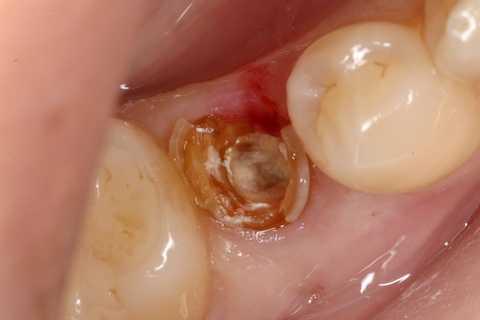

今日の抜歯再植術シリーズ39.2 2025.11.15